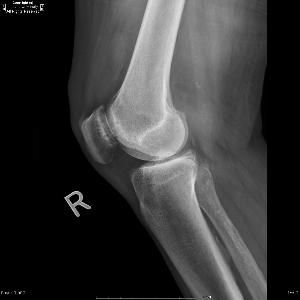

①內分泌性矮小:此類疾病主要是內分泌激素分泌異常所致,包括垂體生長激素分泌過少、甲狀腺功能低下、性早熟、腎上腺皮質激素分泌過多等。②骨疾病性矮小:骨發育不良引起矮小,包括軟骨營養不良軟骨形成不全等。